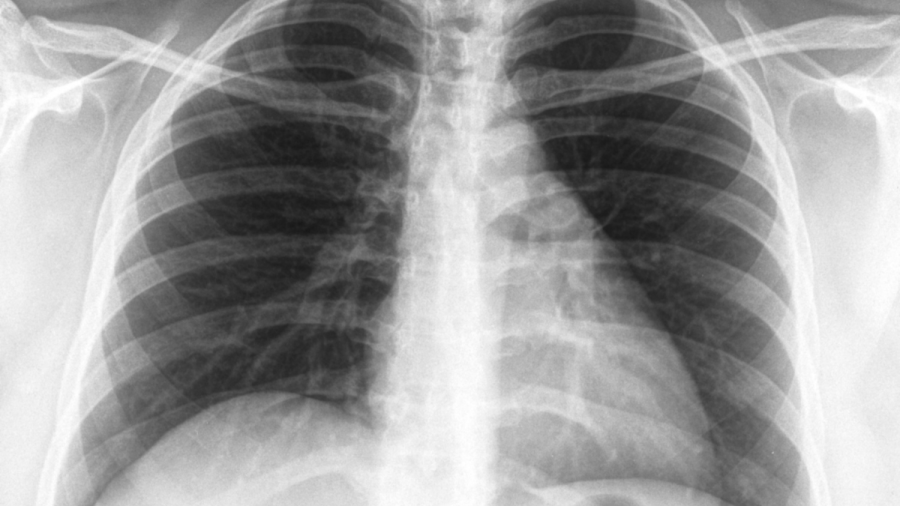

Започва Седмица на отворените врати за туберкулоза, съобщиха на сайта си от Столичната регионална здравна инспекция. Днес се отбелязва Световният ден за борба с туберкулозата.

В България диагностиката, лечението и профилактиката на туберкулозата са безплатни за всички, които се нуждаят, независимо от техния здравноосигурителен статус, посочват на сайта си от Националния център по заразни и паразитни болести. По инициатива на Световната здравна организация, всяка година на 24 март се отбелязва Световният ден за борба с туберкулозата.

Основният начин на предаване на причинителят на туберкулозата е при говор, издишване, кихане, кашляне. Поради високата издържливост на туберкулозните бактерии във външната среда е възможно те да се отделят с храчки, да изсъхват и във вид на вторичен аерозол да бъдат вдишани. В редки случаи причинителят на туберкулозата се предава и при консумация на заразена храна, най-често при консумация на заразено мляко.